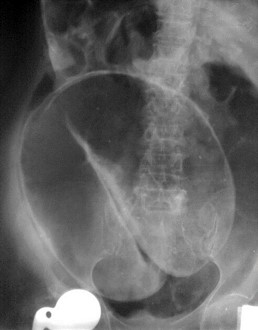

Physical evaluation revealed a middle-aged man who looked healthy, not anaemic and no lymphadenopathy. Abdominal and per rectal examination revealed no abnormal findings and central nervous examination was normal. A barium meal Figure 1 revealed a symptomatic redundant sigmoid colon. A diagnosis of ‘symptomatic redundant sigmoid colon’ grade III [5] was made.

Figure 1: Redundant sigmoid colon (Barium enema X-ray).

Sigmoid colon passed the midline.